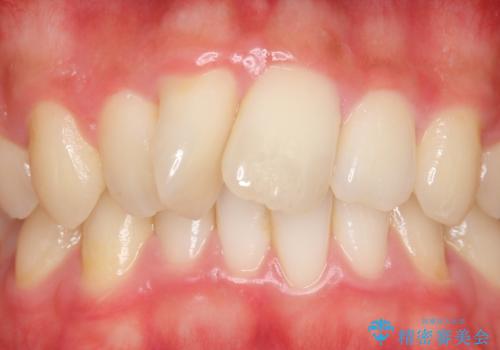

- 上顎前歯の歯並びが気になるが仕事が忙しく矯正治療は難しいため、セラミック矯正で綺麗にしたいといらっしゃった方の症例です。

左右の1番目の歯は傾きが大きいため、セラミッククラウンにするにあたり神経治療を行うことを御了承頂いた上で、前歯4本をオールセラミッククラウン(スペシャル)により補綴しました。